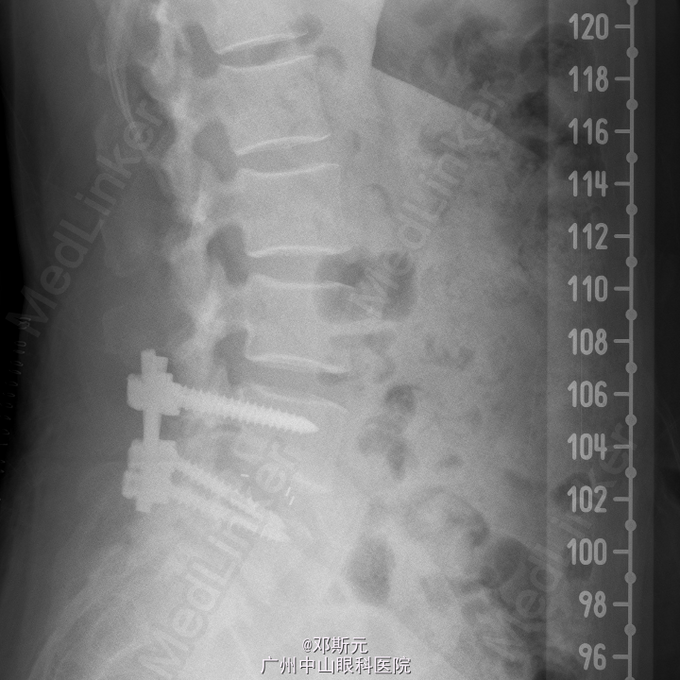

诊断:腰椎滑脱症(L4);腰椎间盘脱出症(L4/5);腰椎间盘突出(L2/3、L3/4、L5/S1)。术前检查未见明显异常,全麻下行“腰椎滑脱复位、椎间盘切除、椎弓根螺钉内固定、植骨融合术”。

双下肢感觉肌力良好,术后恢复可。